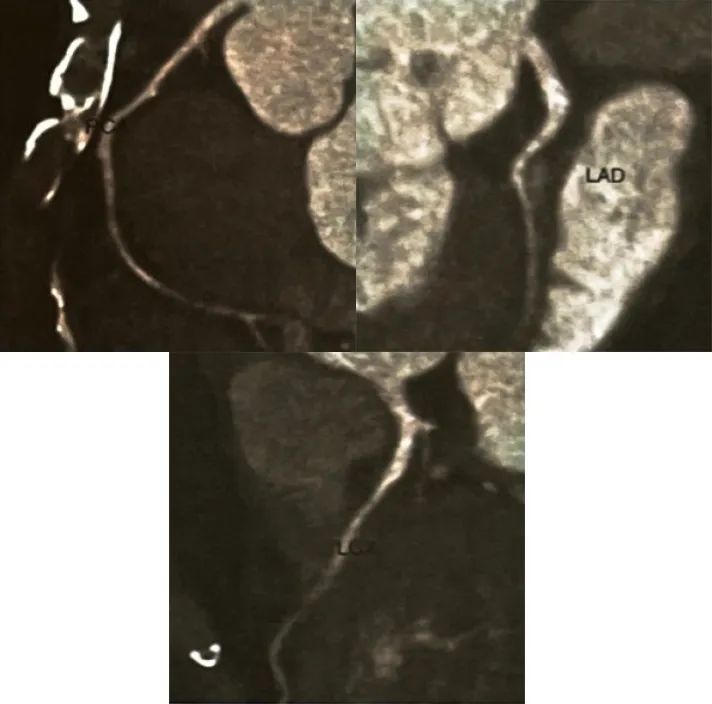

◆动态心电图:①心房颤动伴长间歇(最长RR间期3.2秒);②偶发室性期前收缩;③ST-T改变;④心率变异性分析结果:散点图呈扇形改变。冠状动脉CTA:冠状动脉粥样硬化,前降支中段心肌桥(图3)。

图3. 冠状动脉CT血管成像曲面重组图